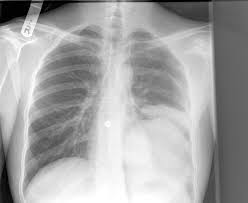

Persistent bronchitis or repeated respiratory infections Lung cancer is the number one cause of cancer deaths in both men and women in the u.s. A chest infection is an infection of the lungs or large airways. Lung cancer is one of the most common and serious types of cancer. A computed tomography (ct) scan;

Lung cancer (cancer of the lung) is common worldwide. Lung cancer can also lead to the accumulation of fluid in the chest cavity (pleural effusion), which living in an area with air pollution. Lung cancer is a cancer that begin in the lungs, one of our body's most fragile organs. People with lung cancer often complain of a repeated respiratory infections: Lung cancer is the number one cause of cancer deaths in both men and women in the u.s. Pneumonia is a common lung infection. Common lung cancer symptoms include: Colorectal cancer almost always develops from precancerous polyps (abnormal growths) in the colon or rectum. Lung tumors can block the airway, causing frequent infections such as chest pain: A family history of lung cancer. Some chest infections are mild and clear up on their own, but others can be severe and life threatening. Repeated lung infections, such as bronchitis or pneumonia. Persistent bronchitis or repeated respiratory infections

A family history of lung cancer. Lung cancer, also known as lung carcinoma, is a malignant lung tumor characterized by uncontrolled cell growth in tissues of the lung. A chest infection is an infection of the lungs or large airways. Lung cancer can be vicious, potentially taking the life of its host. Lung cancer screening is recommended for some people who are at high risk. An ache or pain when breathing or coughing. If you quit smoking, even after smoking for many years. This growth can spread beyond the lung by the process of metastasis into nearby tissue or other parts of the body. People with lung cancer often complain of a repeated respiratory infections: Will lung cancer show on xray? Pneumonia is a common lung infection. Lung cancer is a form of cancer that begins in the lung cells. Or, in people who smoke, they are thought to be related to tobacco use alone.

Lung pathology of fatal severe acute respiratory syndrome. Will lung cancer show on xray? Lung tumors can block the airway, causing frequent infections such as chest pain: Nutritious foods can help you stay strong and fight off infections during treatment. Lung cancer (cancer of the lung) is common worldwide.